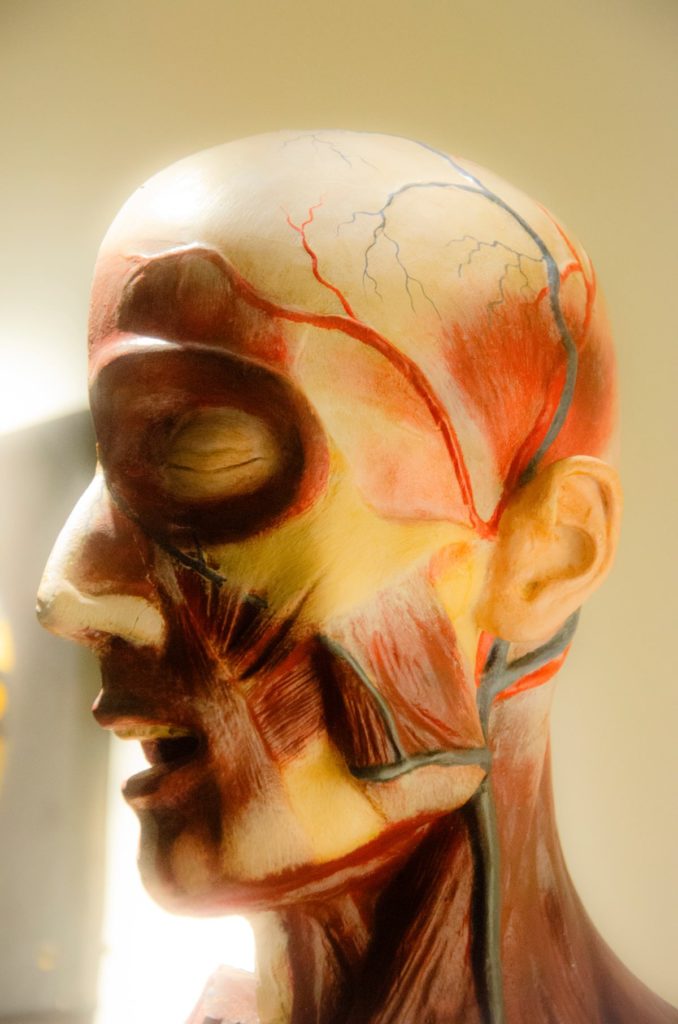

Modelos anatómicos y enseñanza científica

A comienzos del siglo XIX la descripción morfológica del cuerpo humano alcanza gran nivel de detalle. Se consolida el conocimiento anatómico como pilar imprescindible de la medicina científica. A partir de 1800, los modelos anatómicos empiezan a ser una herramienta valiosa para su correcta enseñanza.

Nuevos campos de estudio de la anatomía permiten a lo largo del siglo XIX comprender la realidad biológica de los seres vivos, progresando también la medicina científica. Y gracias a la popularización de los modelos, ese conocimiento puede llegar a los diferentes niveles de enseñanza.

La presencia de modelos de anatomia humana en los gabinetes Bergara está documentada ya en 1793. Los modelos que se han conservado hasta hoy son modelos más tardíos, de finales del XIX.

galeria de imagenes